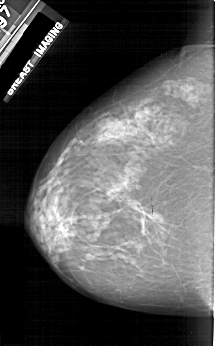

A_1924_1.LEFT_CC

LEFT_CC LINES 5176 PIXELS_PER_LINE 3271 BITS_PER_PIXEL 12 RESOLUTION 43.5 NON_OVERLAY